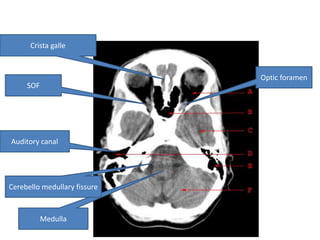

Crista galle Optic foramen SOF Auditory canal Cerebello medullary fissure Medulla

Crista galle

Optic foramen

SOF

Auditory canal

Cerebello medullary fissure

Medulla